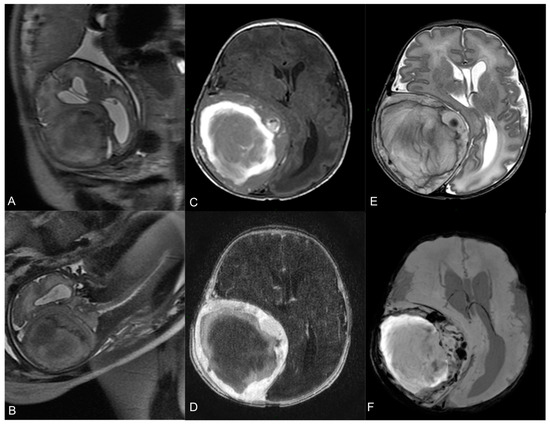

2.1. Presentation and Clinical Characteristics

2.2. Endovascular Embolization and Surgical Treatment